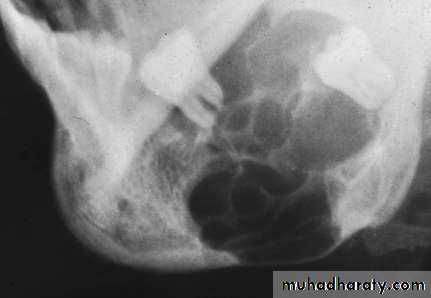

• Radiography:• Uni or Multilocular radiolucent areas

• Soap bubbles

• Copyright 2003, Elsevier Science (USA). All rights reserved.• Ameloblastoma

• Radiography:

• Soap bubbles appearance

• Radiography:• Typically appears as multi locular radiolucent area with well defined scalloped margin or soap bubble.